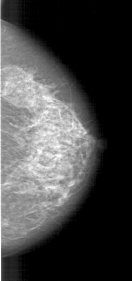

A_1461_1.RIGHT_MLO

RIGHT_MLO LINES 5896 PIXELS_PER_LINE 2881 BITS_PER_PIXEL 12 RESOLUTION 43.5 NON_OVERLAY